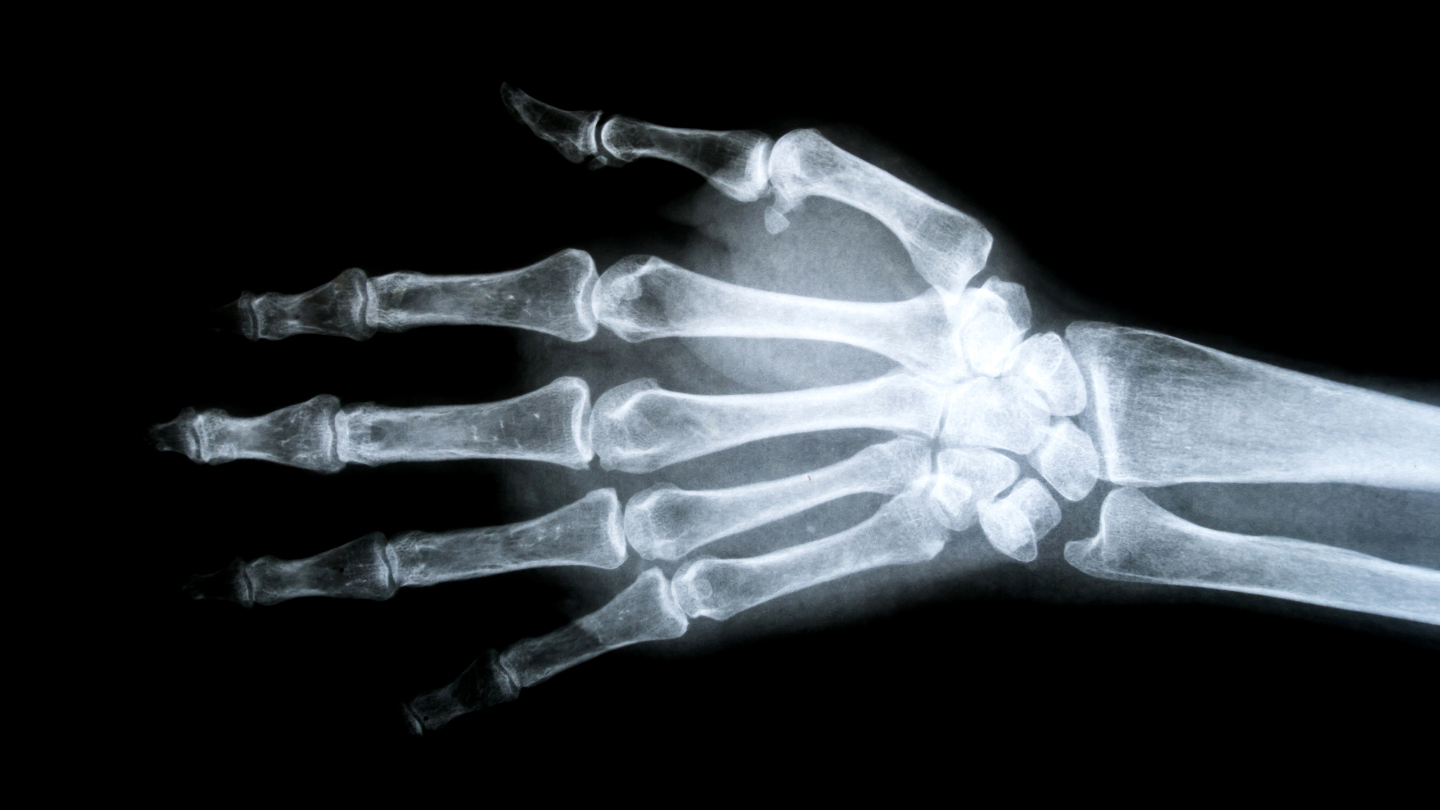

«Непробиваемые» кости

Обычная человеческая кость ломается при нагрузке около 4000 ньютонов. Это как если бы на вас встал взрослый бегемот. Но не целиком, а только одной ногой. Правда, есть важное уточнение: человеческие кости не ломаются от статического веса. В реальности перелом происходит от резкого удара или нагрузки, когда вся эта энергия выделяется за доли секунды.

У людей с редкой мутацией в гене LRP5 показатель в разы выше. Например, после серьезной автомобильной аварии человек может встать без единого перелома. Именно это произошло с одной семьей из штата Айова, США, когда их автомобиль перевернулся несколько раз. Рентген показал: их кости не просто крепкие — они в восемь раз плотнее нормы! Чтобы сломать такую кость, потребовалась бы сила, сопоставимая с весом груженого внедорожника или небольшого слона.

Такая мутация — одна из самых редких в мире. Ученым известно не более десятка семей с этой особенностью. Интересно, что обладатели «суперкостей» часто даже не подозревают о своей уникальности до первого несчастного случая, когда врачи фиксируют невероятный факт: кости выдерживают нагрузки, которые для обычного человека были бы фатальными.